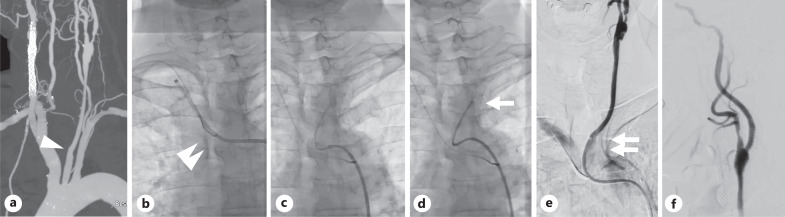

Introduction: During carotid artery stenting (CAS), safe navigation of the guiding catheter (GC) is essential for the success of procedures. However, in cases where stenosis or floating thrombi are located in the common carotid artery (CCA), especially for proximal lesions, advancing the GC without touching the lesions is often difficult. We describe a preliminary experience of the "no-touch" technique for navigating the GC to the CCA using an inner catheter with a specifically designed shape and stiffness optimized to overcome tortuous anatomy.

Methods: We retrospectively reviewed CAS procedures involving the "no-touch" technique for treating stenotic lesions in the CCA. A 4-Fr Newton-shaped stiff catheter was positioned in the CCA. Given its high stiffness and dedicated shape, contact with the lesser curvature of the aortic arch absorbed kickback force. Then, a 6-Fr intermediate catheter and an 8- or 9-Fr balloon GC were coaxially advanced in sequence to the target position without guidewire support, ensuring "no-touch" with the plaques. Patient characteristics, aortic arch type, lesion location, and periprocedural complications were recorded.

Results: The technique was applied to eight procedures (six left-sided lesions) in 7 patients (median age, 76 years; six men) among 53 CAS procedures performed on 49 patients. Lesions were located at the proximal CCA (four procedures) or the carotid bifurcation (four procedures). Three patients had floating thrombi, and four had type III aortic arches. GCs were successfully navigated without touching the lesions in all cases, with no periprocedural complications.

Conclusion: The "no-touch" technique with a Newton-shaped stiff catheter is useful and feasible for navigating the GC in treating stenotic lesions in the CCA, particularly with tortuous anatomy, proximal lesions, and vulnerable plaques.